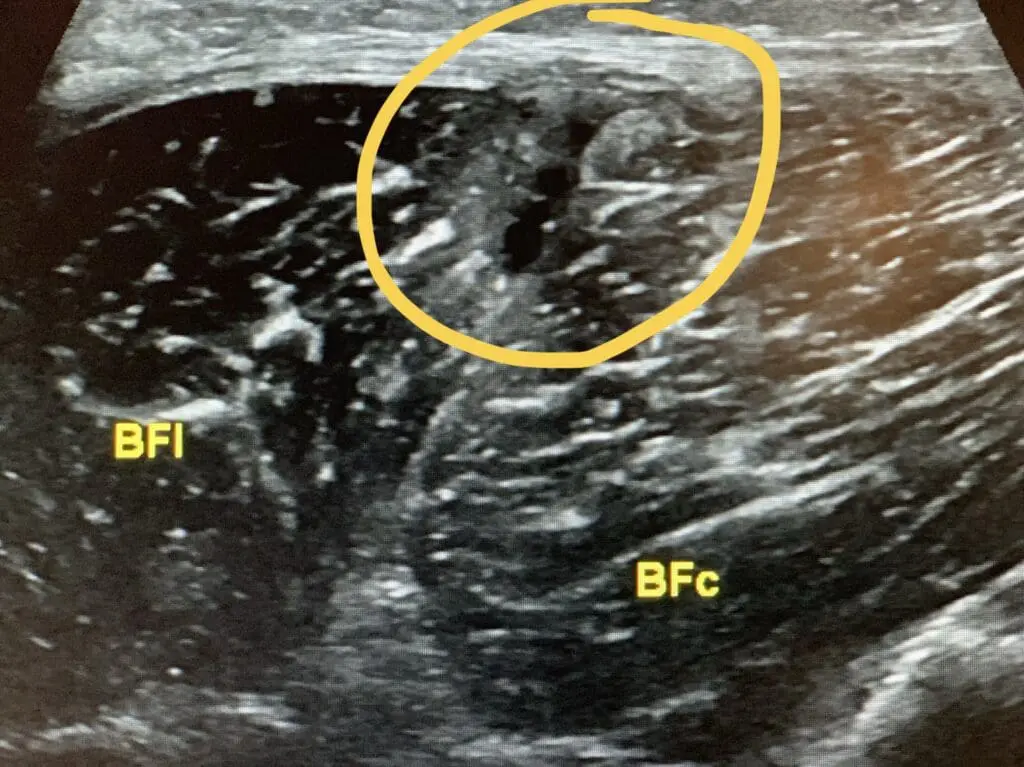

Rotura muscular en UMC de las dos cabezas del bíceps femoral en futbolista profesional. Iniciamos tratamiento con @EPI_Advanced